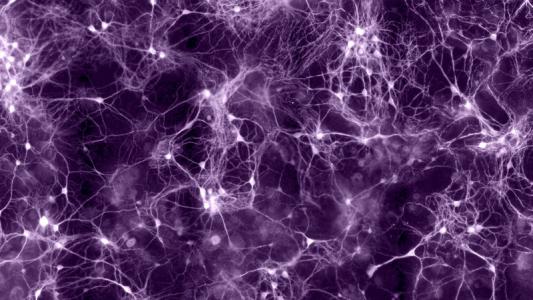

Hacking the brain's comms network – without surgery

When nerve cells in the brain communicate, they create tiny electric fields that can be sensed – and sometimes...